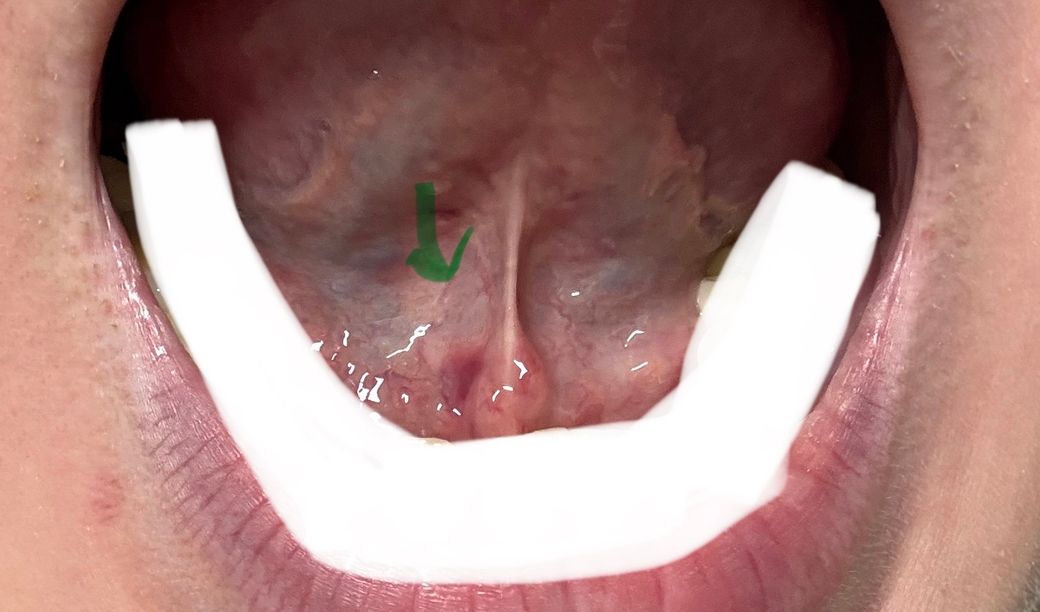

혀아래에 물집 짜려다가 혈관이 터진것 같은데 괜찮을까요?

혀 아래에 물집이 큰게 나서 손톱으로 몇번 짜려고 힘줬더니 터지지는 않았지만 혈관이 터진것 같은데 괜찮은걸까요? 연휴라 둬도 되는지 걱정입니다.

• 1번 째 사진

사진으로 봤을 경우에는 크게 문제가 없어 보입니다 혀 아래 혈관 등을 무리하게 만지게 되면 연조직에 손상이 생기기 때문에 건들지 않는 것이 좋습니다